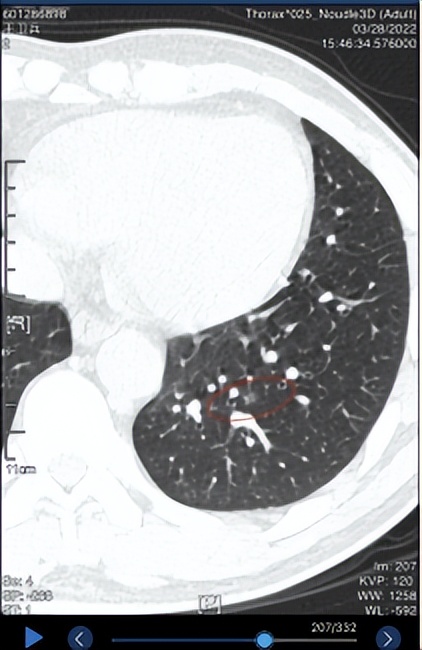

3. 2022.1.26日复查,SE4/7IMG70右肺上叶尖段见一混合密度影,病灶形态类圆形,边界不清晰,无分叶,有毛刺,有胸膜牵拉,无血管束集征,无空泡征。病灶前后径 12.6 mm,左右径 8.8 mm,上下径 18.7 mm。病灶平扫时密度为 -88HU。左肺下叶后基底段(SE4/7,IM205)见一枚磨玻璃结节,内见空泡影,长径约6mm。 右肺中叶及左肺上叶舌段少许斑片索条影。 两肺门区未见异常密度影。 胸膜未见增厚改变。 纵隔内未见异常密度影。